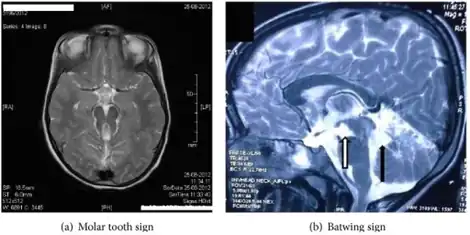

a) Hypoplastic superior cerebellar peduncles form “molar tooth appearance.” b) “batwing appearance” in fourth ventricle.

Detection of the hypoplasia of the cerebellar vermis is achieved through a cranial magnetic resonance imaging (MRI) scan. The presence of the ‘molar tooth sign’ (MTS) on the MRI scan,  a mid- brain hind- brain malformation, confirms this condition and is a key indicator of COACH syndrome. The MTS's distinguished shape is attributed to the lengthened superior cerebellar peduncles and deepened interpeduncular fossa.[6] To diagnose ataxia, both neurological assessment and physical examination are required. This can include MRI scans, study of behavior and motor skills in infancy and analysis of family history and genetics. In the case of congenital ataxia, patients are born with the condition and thus diagnosis is more difficult, therefore diagnosis of ataxia alone is not sufficient to indicate COACH syndrome, and must be used in conjunction with other symptoms.[10] Oligophrenia, more commonly known as intellectual disability, is diagnosed using personalized testing to measure intelligence and physical examination for anomalies and facial dysmorphia.[14] Hepatic fibrosis has a range of diagnostic techniques, including invasive and non- invasive. Liver biopsy examination is an invasive technique, which uses liver tissue extracted from the patient to identify the degree and severity of the fibrosis, and may also provide insight on tumor growth. Ultrasonography- based tests use radiation waves to measure the stiffness of the tissue and are non- invasive. Serum tests are also non- invasive, and diagnose liver complications on the basis of the amount and presence of certain proteins and chemicals in the body.[15] Kidney cysts can be discovered using ultrasound techniques, and monitoring of the patient's urine concentrating ability for any abnormalities can indicate other renal complications such as nephronophthisis.[6][7]